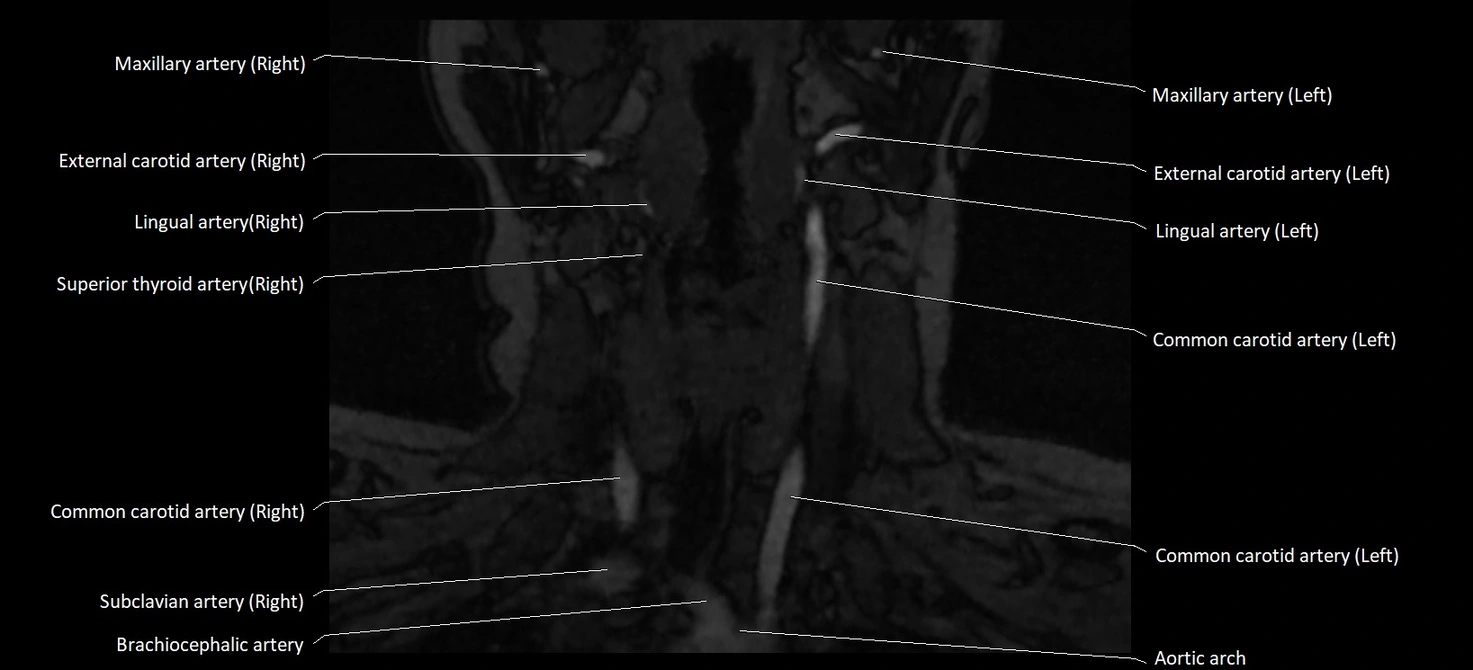

MRI Appearance:

• T1-Weighted Images:

• Appears as a tubular, hypointense (dark) structure relative to muscle

• May show flow void if the blood flow is fast

• T2-Weighted Images:

• Typically hypointense or isointense to muscle, but can be hyperintense if slow flow or stasis is present

• STIR (Short Tau Inversion Recovery):

• Vein remains hypointense, but surrounding edema or inflammation will appear hyperintense

MRI images

image